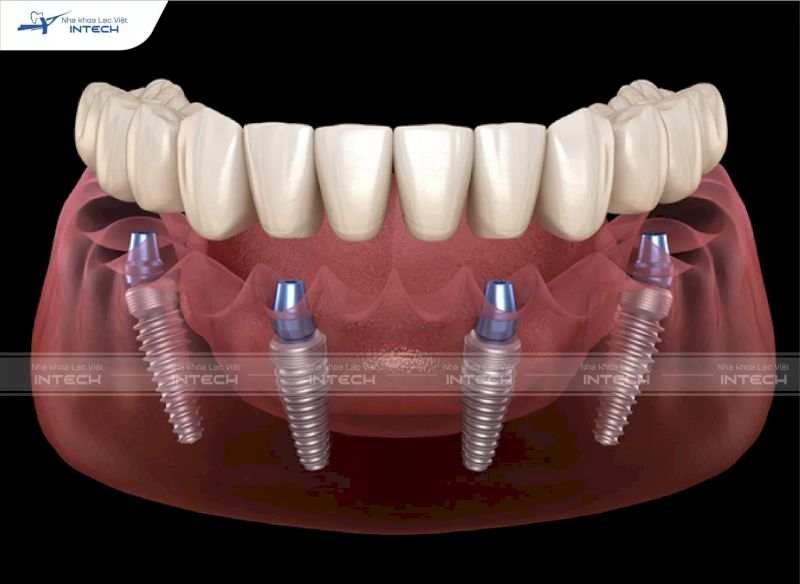

Implant Titanium là loại trụ Implant được chế tác từ Titanium – kim loại nhẹ, bền và có khả năng chống ăn mòn vượt trội. Đây cũng là vật liệu được sử dụng phổ biến trong y khoa nhờ đặc tính an toàn, không gây phản ứng với cơ thể và tương thích sinh học cao. Titanium thường xuất hiện trong các ứng dụng y khoa như chế tạo khớp gối, khớp háng, xương chậu nhân tạo...

Trong lĩnh vực trồng răng Implant, Titanium được sử dụng để làm trụ Implant – phần trụ cố định gắn vào xương hàm thay thế cho chân răng đã mất. Ngoài ra, Titanium còn được dùng để chế tác trụ phục hình, giúp hỗ trợ kết nối với mão răng sứ phía trên. Nhờ các đặc điểm nổi bật của Titanium, trụ Implant không chỉ bền chắc mà còn đảm bảo an toàn lâu dài trong môi trường khoang miệng.